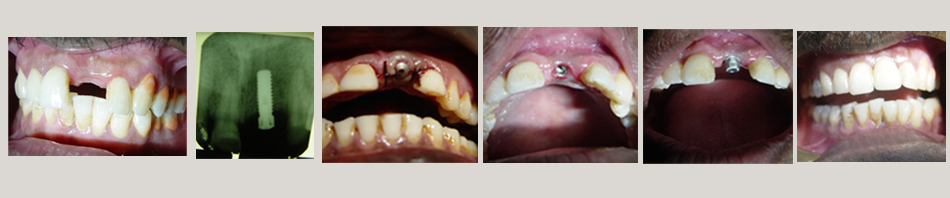

Single Tooth Replacement